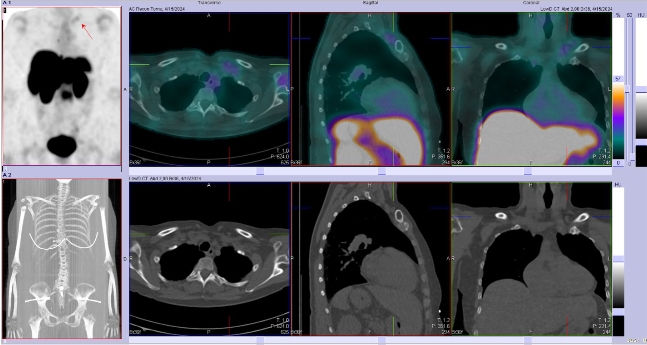

Scintigrafie Octreoscanem

I. v. jsme aplikovali 190 MBq analogu somatostatinu značeného 111In

(přípravek OctreoScan firmy Curium Netherlands B.V.) a provedli pomocí hybridní tomografické scintilační kamery Siemens Symbia Pro.specta X3 opatřené kolimátory pro střední energie planární celotělovou scintigrafii a cílenou tomografickou scintigrafii (SPECT) břicha a pánve kombinovanou s CT.

/ Obr. č. 3: Fúze SPECT/CT 4 hod. po aplikaci OctreoScanu. /

Popis: pozorujeme patologická ložiska zvýšené depozice radiofarmaka-nově nekontrastně ve více LU v levém nadklíčku, v jedné parasternální LU vpravo (úroveň Th6) vel. 10 mm, v LU v dolním mediastinu prekardiálně cca 17 mm, tomograficky zachycena chabě zvýšená akumulace RF v Th páteři v úrovni obratlového těla Th7 a Th8 (v ldCT bez patologického korelátu, nově však v ldCT obraze zjištěna v. s. lýza pravého postranního výběžku obratle Th8), v levém jaterním laloku - S4b, v pravém jaterním laloku - S5 a S6, v LU paraaortálně v úrovni L2/3 15,5 mm - dnes okrsek nápadnější, chabě v levé kosti kyčelní dorsálně při SIS - částečná regrese od min. vyšetření.

Nález svědčí pro přítomnost vícečetných patologických ložisek zvýšené denzity somatostatinových receptorů ve výše uvedených lokalizacích. Ve srovnání s posledním vyšetřením jsou detekována nová ložiska v levém nadklíčku a mediastinu, susp. diskrétní nález i v Th páteři (obratel Th7 a Th8) se zachycenou lýzou postranního výběžku obratle Th8 vpravo v CT obraze, částečná regrese okrsku v levé kosti kyčelní oproti minulému vyšetření.

Závěr:

U nyní 70leté ženy s neuroendokrinním tumorem nejasného primárního zdroje prokazujeme progresi nálezu oproti vyšetření před 22 měsíci.